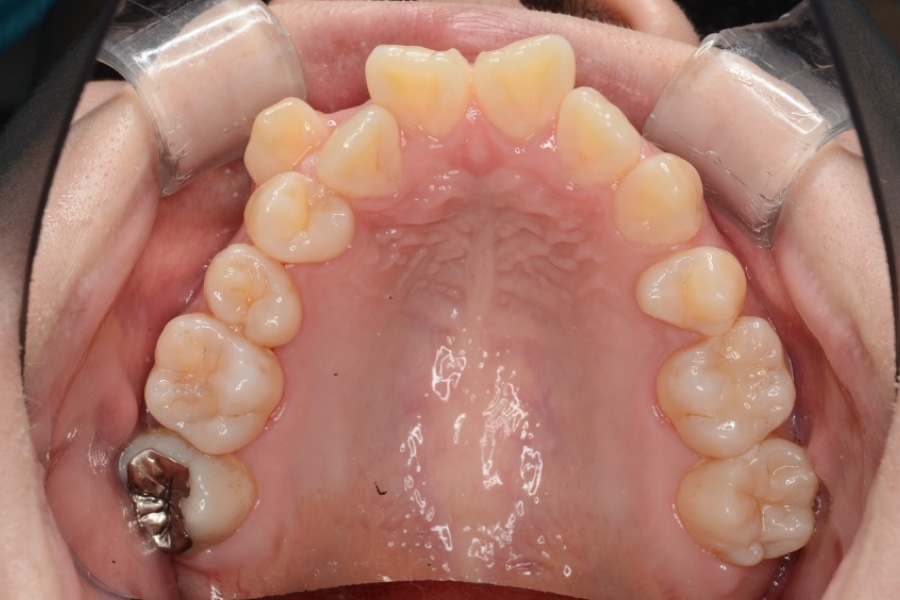

治療前

主訴 全体のガタつきが気になる

期間 2年

費用 220,000円〜660,000円

治療内容 インザライン矯正

小臼歯抜歯